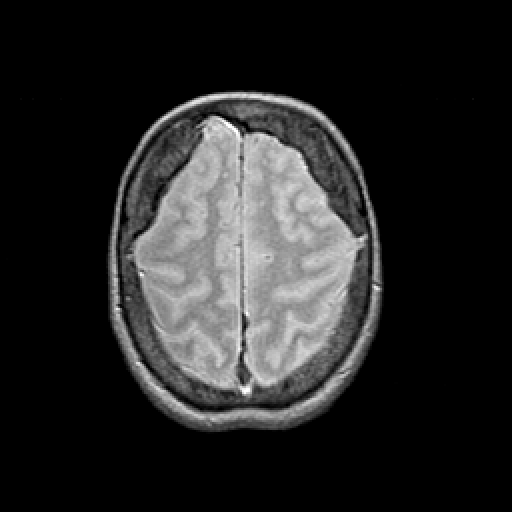

Proton density-weighted structural MR: Slice 42

Slice 42